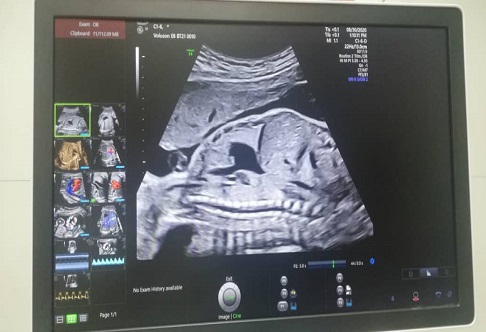

دستگاه سونوگرافی برند GE مدل ولوسان E8 در بیمارستان نفت امام خمینی (ره) نصب و راه اندازی گردید.

به گزارش پایگاه اطلاع رسانی بهداشت و درمان صنعت نفت آبادان امروز ۲۸ تیر ۱۴۰۱ دستگاه سونوگرافی برند GE مدل ولوسان E8 یکی از بروزترین دستگاههای حال حاضر در مرکز رادیولوژی بهداشت ودرمان صنعت نفت آبادان در حال نصب و آموزش می باشد. تلاشها و زحمات ارزشمند دکتر مهدی هاشمی مدیر عامل سازمان در صدور مجوز با هدف ارائه خدمات بهتر به مراجعین بسیار قابل تقدیر است و همچنین تلاش ، برنامه ریزی و پیگیری مجدانه دکتر نصراله حسونی بحرینی رییس بهداشت ودرمان صنعت نفت آبادان که این دستگاه در بیمارستان امام خمینی (ره) نصب و راه اندازی شد.

غلامرضاحیدری مسئول رادیولوژی بیمارستان نفت آبادان افزود :این دستگاه یکی از برند های محبوب و معروف و بروز ترین دستگاه در حال حاضر می باشد و با توجه به نقش بسیار مهم بخشهای پاراکلینیکی در روند تشخیص بیماری، این دستگاه سونوگرافی در زمینه سرعت بخشیدن به روند تشخیص و درمان جمعیت تحت پوشش و ارائه خدمات درمانی بیشتر خریداری ، نصب و راه اندازی شد. امید است همچنان با پیگیری های دکتر حسونی بحرینی و عزم راسخ مدیر عامل سازمان جهت پیشبرد اهداف بهداشت ودرمان صنعت نفت ، با بهره مندی از تجهیزات استاندارد و به روز باعث ارتقاء کمّی و کیفی خدمات تشخیصی برای مردم شهید پرور آبادان باشیم.